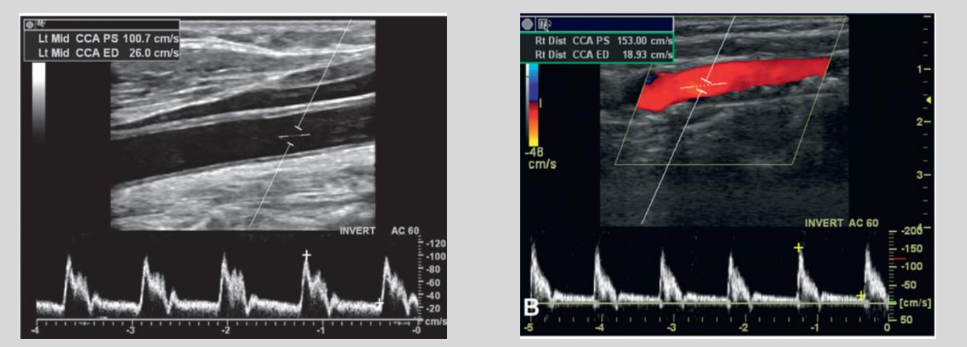

what is this waveform showing?

Cardiac Arrythmia: irregular heartbeat

Cardiac Arrythmia